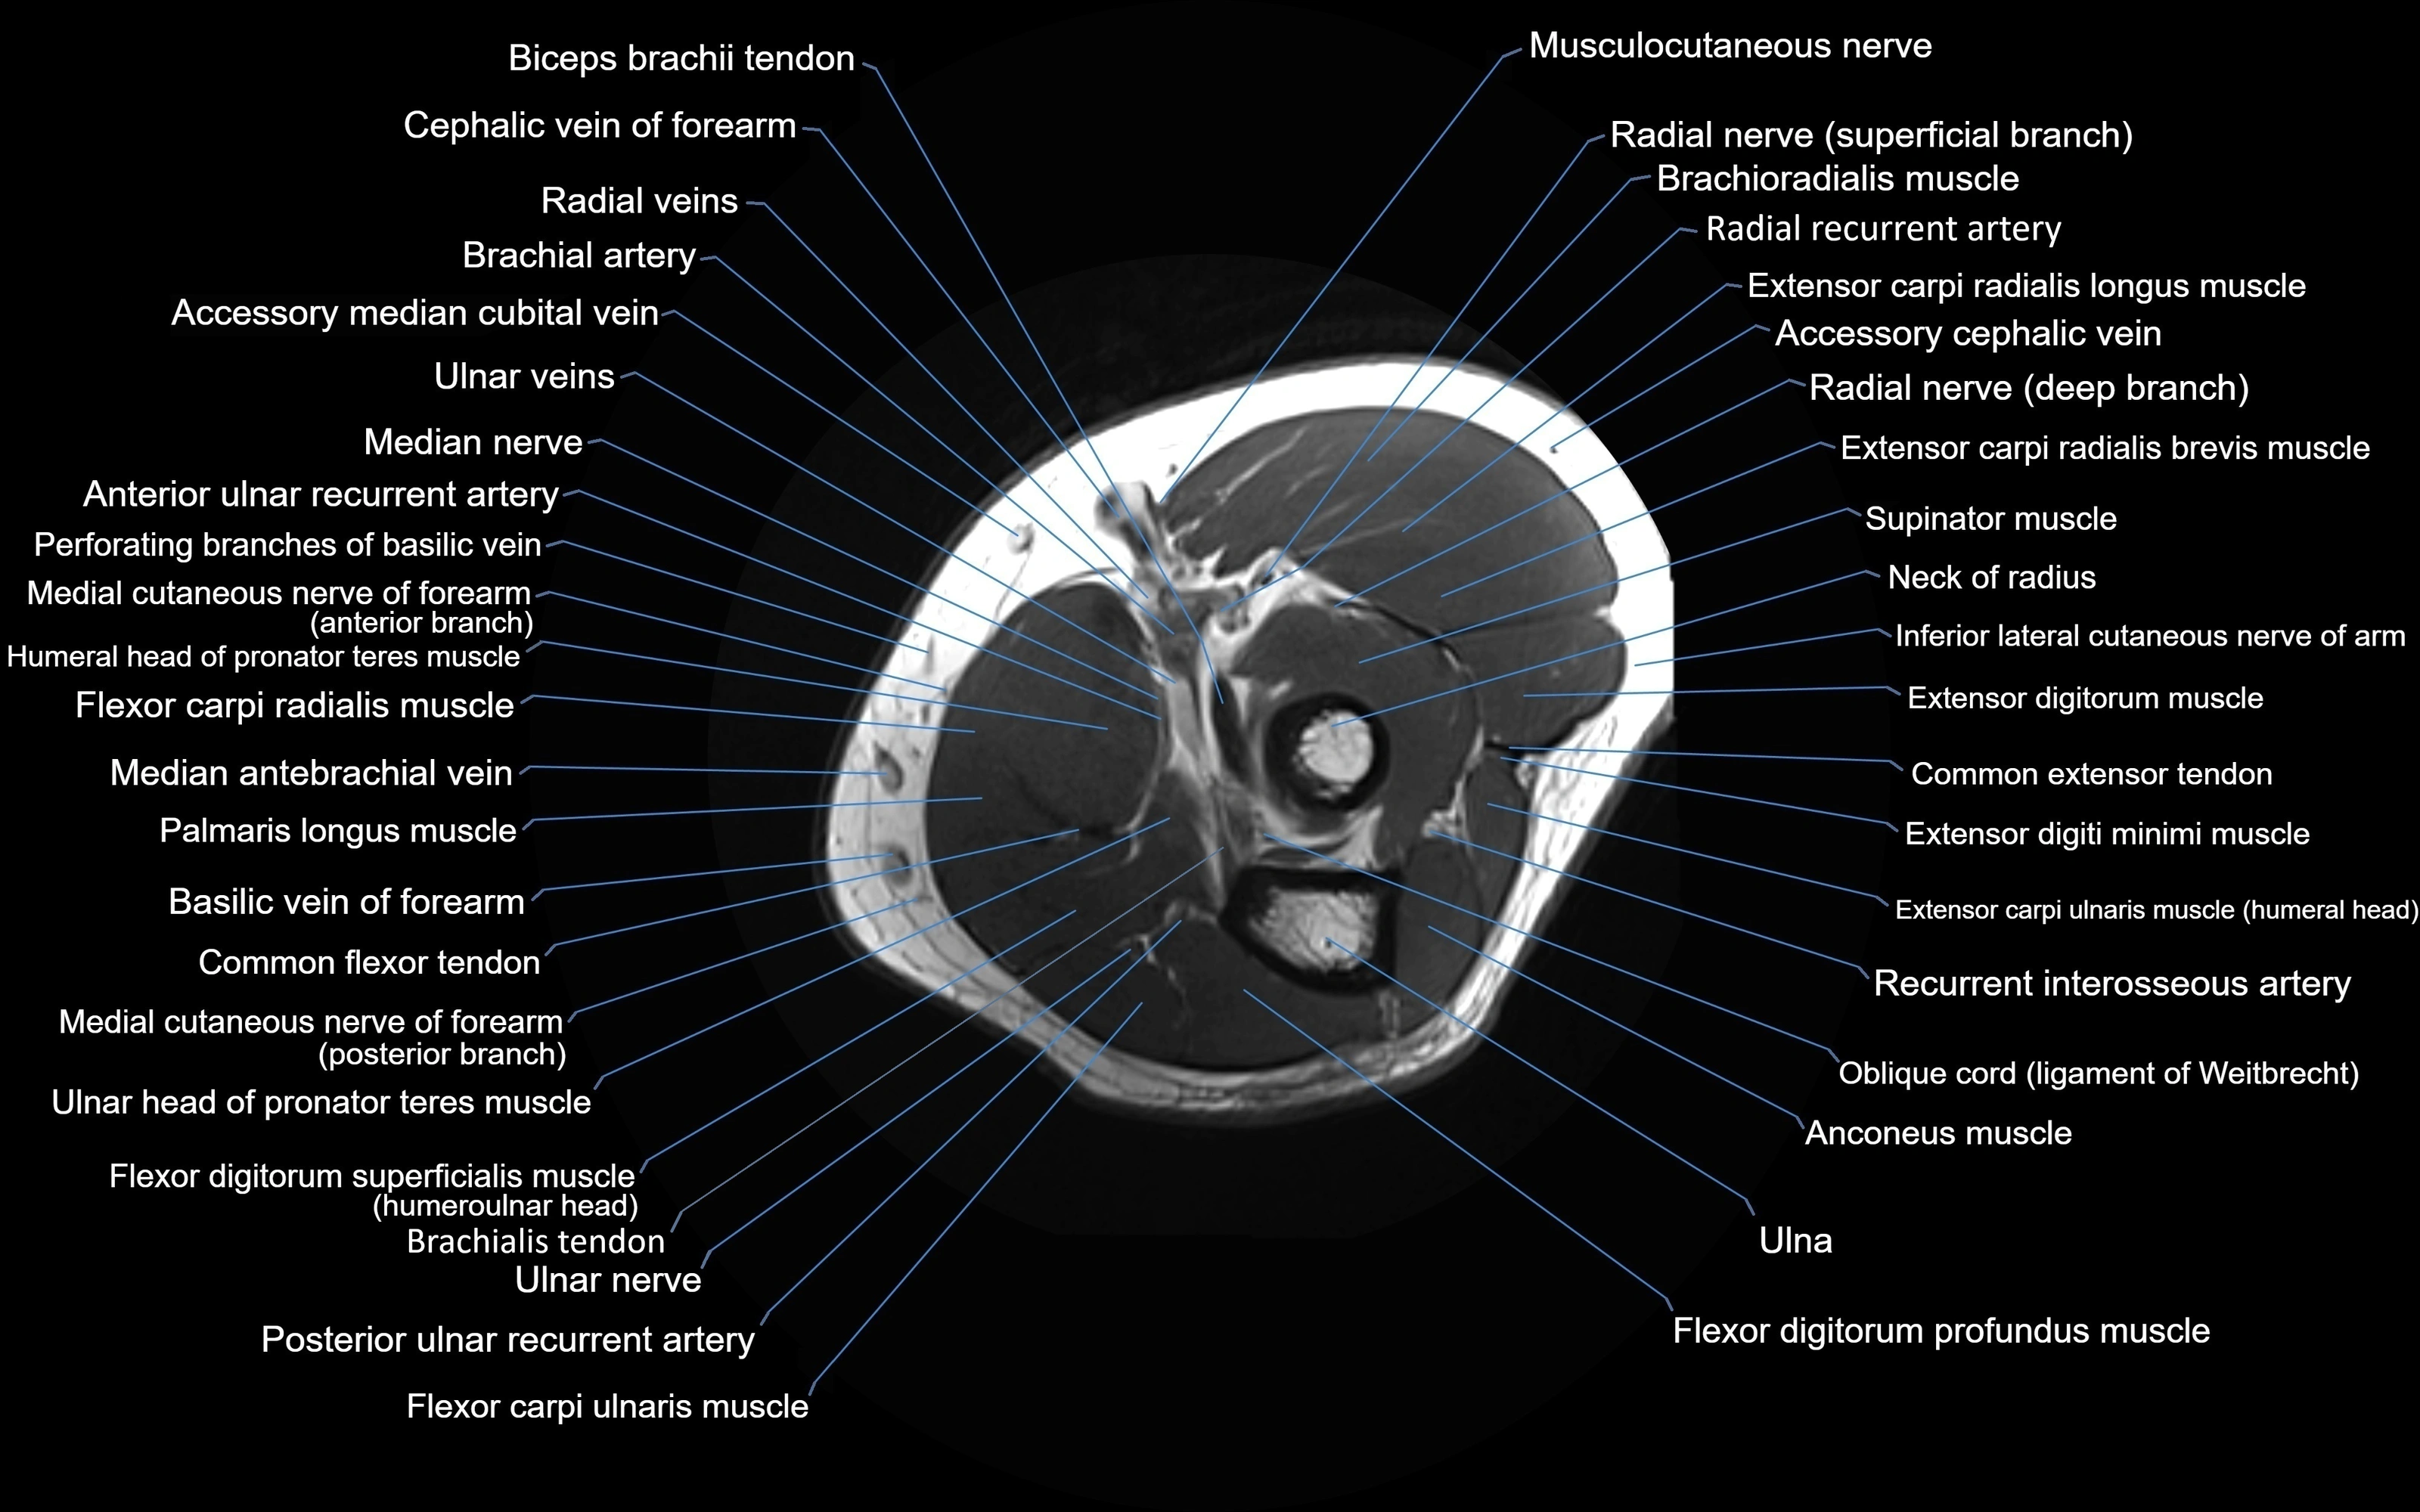

MRI image

image